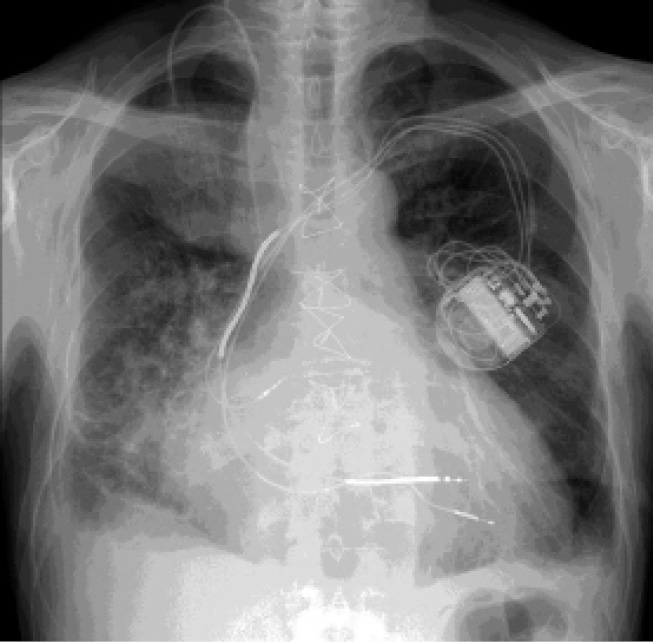

Современная методика, которая успешно зарекомендовала себя в лечении пациентов, страдающих тяжелой СН, – модуляция сердечной сократимости (МСС) с использованием устройства Optimizer® (Impulse Dynamics, Orangeburg, NY, USA), последним поколением которого является Optimizer Smart® с двумя желудочковыми электродами (рис. 5). Данная методика применима у пациентов, страдающих СН нФВ (ФВ ЛЖ 25–45%) и узким комплексом QRS (<130 мс), для повышения физической активности, качества жизни и уменьшения выраженности клинических проявлений СН.

Рис. 5. Модулятор сердечной сократимости